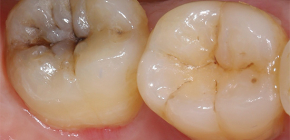

Nella maggior parte dei casi, un forte dolore pulsante nel dente indica lo sviluppo della pulpite. In una situazione del genere, in nessun caso puoi sperare che gli antidolorifici aiuteranno a risolvere completamente il problema e il dolore scomparirà gradualmente. Un urgente bisogno di curare un dente, senza portare a complicazioni della pulpite, alcune delle quali possono persino minacciare la vita di una persona. L'odontoiatria moderna consente un trattamento strumentale e hardware di alta qualità della pulpite secondo nuovi metodi e quasi senza dolore (soprattutto se confrontato con i tempi sovietici). Qual è il vantaggio dei moderni metodi di trattamento, in cosa consistono e quali sono i principi di determinazione del prezzo per il trattamento della pulpite - questo sarà discusso più avanti.